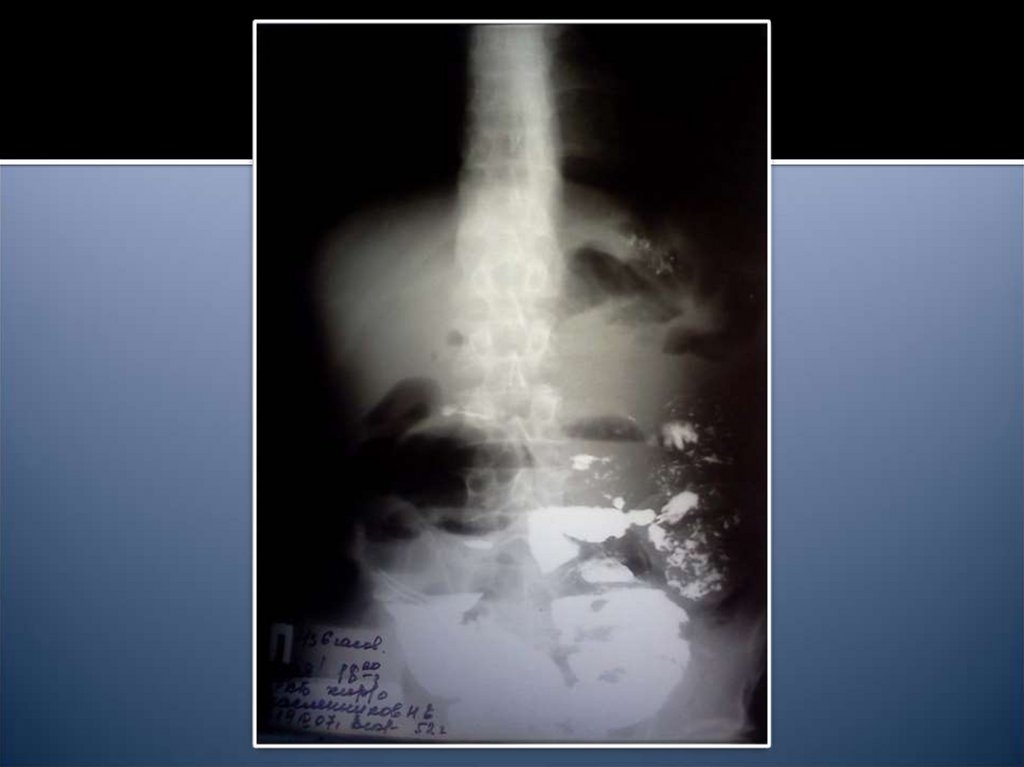

14. Рентгенологические признаки

Чаши Клойбера

Симптом Кивуля (аркады)

Проба Шварца

Пневматоз петель кишечника